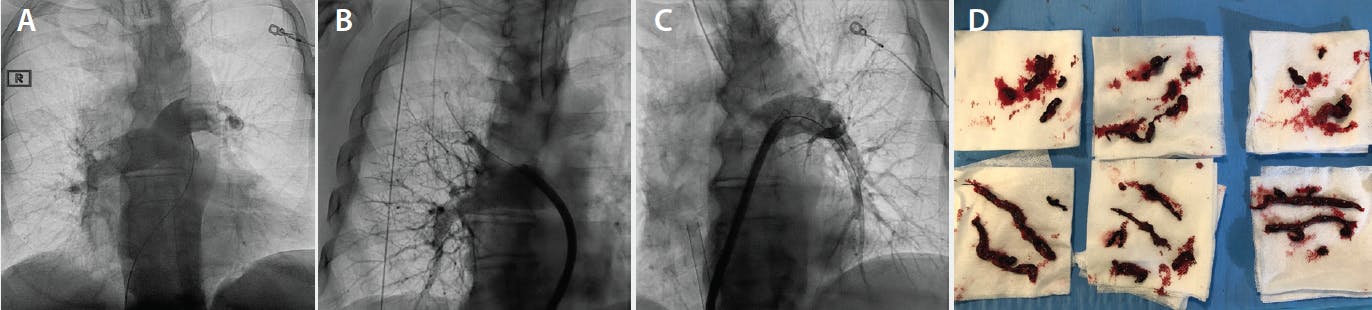

Current data show that ECMO with anticoagulation alone can eventually lead to sufficient RV recovery to allow for decannulation.9 However, these patients will likely require prolonged circulatory support, therefore exposing them to increased complications. In the authors’ opinion, in the current era in which several percutaneous reperfusion tools are now available, ECMO should be primarily used in conjunction with a reperfusion strategy. RV strain is markedly improved within 24 to 48 hours with percutaneous intervention, faster than with anticoagulation alone.10,11 As far as the choice of reperfusion strategy, thrombolytic utilization is problematic given the large-caliber arterial access and platelet dysfunction and increased probability of bleeding complications. Percutaneous mechanical aspiration thrombectomy (eg, FlowTriever system, Inari Medical) or surgical thrombectomy may be the preferred approach. The former is effective in very acute presentations, whereas surgery may be preferred in later presentations or patients suspected of having a significant chronic component as evidenced by RV hypertrophy or very high pulmonary artery (PA) pressures. Figure 1 describes a case example in which large-bore aspiration thrombectomy was feasible with a multistage venous ECMO cannula in place, and rapid wean of ECMO support was facilitated by the prompt reperfusion of the pulmonary circulation.

Figure 1. A 79-year-old active man with hypertension was evaluated for dyspnea and referred for an exercise stress echocardiogram. While on the treadmill, he experienced marked dyspnea on exertion at low workloads, with intermittent runs of nonsustained ventricular tachycardia (NSVT). He was transferred by ambulance to the emergency department (ED) for expedited cardiac evaluation. During transport, the patient experienced hemodynamic decompensation, requiring the initiation of vasopressor therapy. On arrival to the ED, systolic blood pressure was 60 mm Hg, heart rate was 110 bpm, and oxygen saturation was 80% on 6 L of oxygen via nasal cannula. Vasopressor therapy was further uptitrated. The patient continued to have runs of NSVT, with a baseline electrocardiogram suggesting diffuse myocardial ischemia.

Because of concern for acute myocardial infarction, the decision was made for emergent left heart catheterization. An intra-aortic balloon pump was inserted. Left heart catheterization revealed nonobstructive coronary artery disease and a hyperdynamic left ventricle with an LV end-diastolic pressure of 1 mm Hg. Given the high index of suspicion, pulmonary angiography was performed and revealed bilateral central occlusive pulmonary emboli (A). Due to the profound hypoxia and cardiovascular collapse, the patient was intubated and peripheral ECMO was initiated; the patient became asystolic, requiring brief CPR while the ECMO cannulas were being inserted.

After stabilization on ECMO, percutaneous mechanical thrombectomy of the PAs was performed using a 20-F FlowTriever system. A large amount of acute and subacute thrombus was removed from the right and left main PAs, with improved distal perfusion (B–D) and marked improvement in the systolic PA pressure from 84 mm Hg to 38 mm Hg immediately postprocedure. Concurrently, the blood pressure normalized, allowing for discontinuation of vasopressor therapy while in the catheterization lab.

On echocardiography the next day, the right ventricle was mildly dilated with normal function, and there was no change in RV size or function with ECMO weaning. The patient was awake and responsive. He was transitioned off ECMO to 2.5 µg/kg/min of dobutamine, followed by extubation the next day. The patient was discharged home on apixaban therapy 5 days after presentation and was asymptomatic at 1-month follow-up, with an echocardiogram demonstrating normal RV size and function.